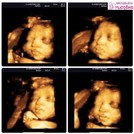

24วีคค่ะ

29w